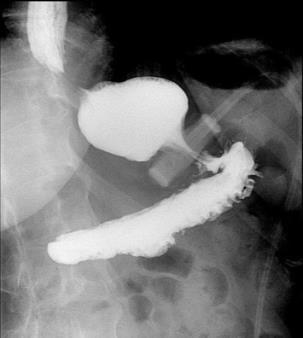

BURKITT LYMPHOMA INDUCED PSEUDOACHALASIA WITH DRAMATIC SYMPTOMATIC IMPROVEMENT POST-CHEMOTHERAPY

Marni H. Wilkoff1 , Emily S. Seltzer1 , Allison E. Wang1,2 , Bruno Almeida Costa1 , Bruce Gelman1

1Mount Sinai Morningside-West Hospitals, Icahn School of Medicine at Mount Sinai, New York, NY, United States;

2Mount Sinai Beth Israel Hospital, Icahn School of Medicine at Mount Sinai, New York, NY, United States 69